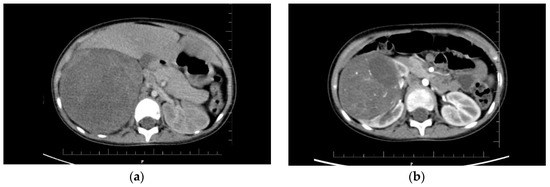

The first twin had Apgar scores of 8-10-10 and a birth weight of 1940 g. At birth, the neonate appeared normal, without any disease or malformation. On day 5 of life, supraventricular tachycardia was diagnosed, which required pharmacological treatment. At 12 months of age, the child required no further cardiac care or treatment. Her psychomotor development was within normal limits. At the age of 3.5 years, the patient was admitted to the emergency room due to hematuria and abdominal pain. Ultrasound examination revealed an enlarged right kidney with a mass in the upper pole measuring 10 × 9 × 12 cm (Figure 1). Chest X-ray showed metastases to both lungs. A computed tomography (CT) scan excluded central nervous system lesions confirmed a tumor in the right kidney and multiple metastatic nodules in both lungs. Based on the clinical picture and imaging studies, Wilms’ tumor was diagnosed in stage IV, and the neoadjuvant chemotherapy according to the SIOP protocol was given [12,13]. After 6 weeks of chemotherapy, a significant reduction in the tumor mass in the kidney was observed in CT scan. Lung metastases were still present, although smaller. A right-sided radical nephroureterectomy was performed, and treatment was continued according to the protocol. In the 11th week of postoperative treatment, the control CT examination of the lungs did not reveal any metastases, so the lung radiotherapy was abandoned. The histopathological result showed a mixed form of nephroblastoma, predominantly epithelioid with residual blastemal compartment, intermediate risk, local stage II (Figure 2). The child is currently 12 months from completion of treatment and remains in full remission of the disease.

Figure 1.

The results of the computed tomography examination in both patients: (a) Visible tumor of the right kidney in the first girl, size 10 × 9.3 × 12.6 cm; (b) Visible tumor of the right kidney in the second child, size 7 × 6.1 × 7.7 cm.

Both sisters received preoperative chemotherapy according to SIOP protocol for stage IV. It lasted 6 weeks and included administration of six doses of VCR 1.5 mg/m2 every week, three doses of actinomycin 45 ug/kg every 2 weeks, and two doses of doxorubicin 50 mg/m2 at week 1 and 5. Tumor’s size on CT examination decreased before and after 6 weeks of chemotherapy, respectively, in the first twin from 10 × 9.3 × 12.6 cm to 5.2 × 4.5 × 6.7 cm, and in the second twin from 7 × 6.1 × 7.7 cm to 3 × 4 × 2.8 cm (Figure 1). In both sisters, mixed form of Wilms tumor, intermediate-risk group, local stage II were diagnosed. Hence, radiotherapy to the abdominal cavity was not used. Postoperative chemotherapy included a 4-drug regimen according to SIOP protocol and lasted 34 weeks.